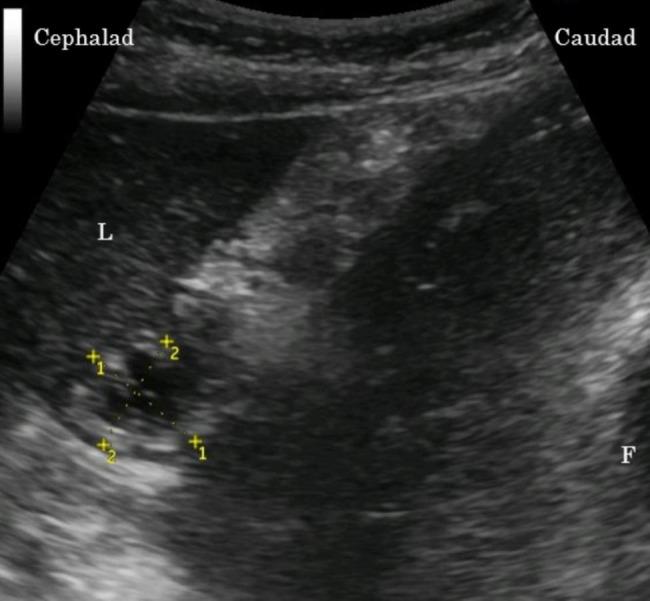

Sixty-three parturients scheduled for cesarean section under combined spinal epidural anesthesia (CSEA) were randomly allocated to one of three groups: Group O received 500 mL ORS before bedtime and 500 mL 2 h before CSEA; Group M received mineral water instead of ORS; and Group C had no fluid intake (controls). After entering the operating room, stomach size was measured using ultrasound. Blood samples were obtained, and CSEA was induced. Vasopressors were administered when systolic blood pressure was < 90 mmHg or decreased by > 20%. As a vasopressor, phenylephrine (0.1 mg) was administered at ≥ 60 beats/min heart rate or ephedrine (5 mg) at < 60 beats/min heart rate. The primary outcome was the total number of vasopressor boluses administered. Secondary outcomes were the cross-sectional area of the stomach antrum, maternal plasma glucose levels, serum sodium levels, total intravenous fluid, bleeding volume, urine volume, operative time, and cord blood gas values after delivery.

63 例行椎管内-硬膜外联合麻醉(CSEA)剖宫产的产妇随机分为三组:O 组于睡前和 CSEA 前 2 小时分别口服 500ml ORS;M 组给予矿泉水代替 ORS;C 组(对照组)无液体摄入。进入手术室后,使用超声测量胃的大小。采集血样,并进行 CSEA。当收缩压<90mmHg 或下降>20%时给予血管加压药。当心率≥60 次/分时给予去氧肾上腺素(0.1mg),当心率<60 次/分时给予麻黄碱(5mg)作为血管加压药。主要结局为血管加压药的总推注次数。次要结局为胃窦横截面积、产妇血浆葡萄糖水平、血清钠水平、总静脉输液量、出血量、尿量、手术时间和分娩后脐血血气值。